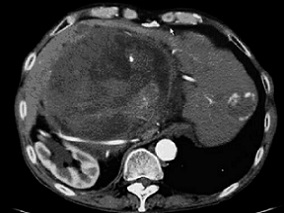

1小时条评论【病例介绍】 男,62岁,主因发现腹部肿物18年,腹痛腹胀1年半,加重2个月入院。患者18年前体检时发现腹部肿物,当时无不适症状,肿瘤直径约11cm,于外院行剖腹探查,因肿物位于腹膜后间隙、邻近腹主动脉及下腔静脉,未能切除,仅切取部分肿瘤组织行病理检查,报告...